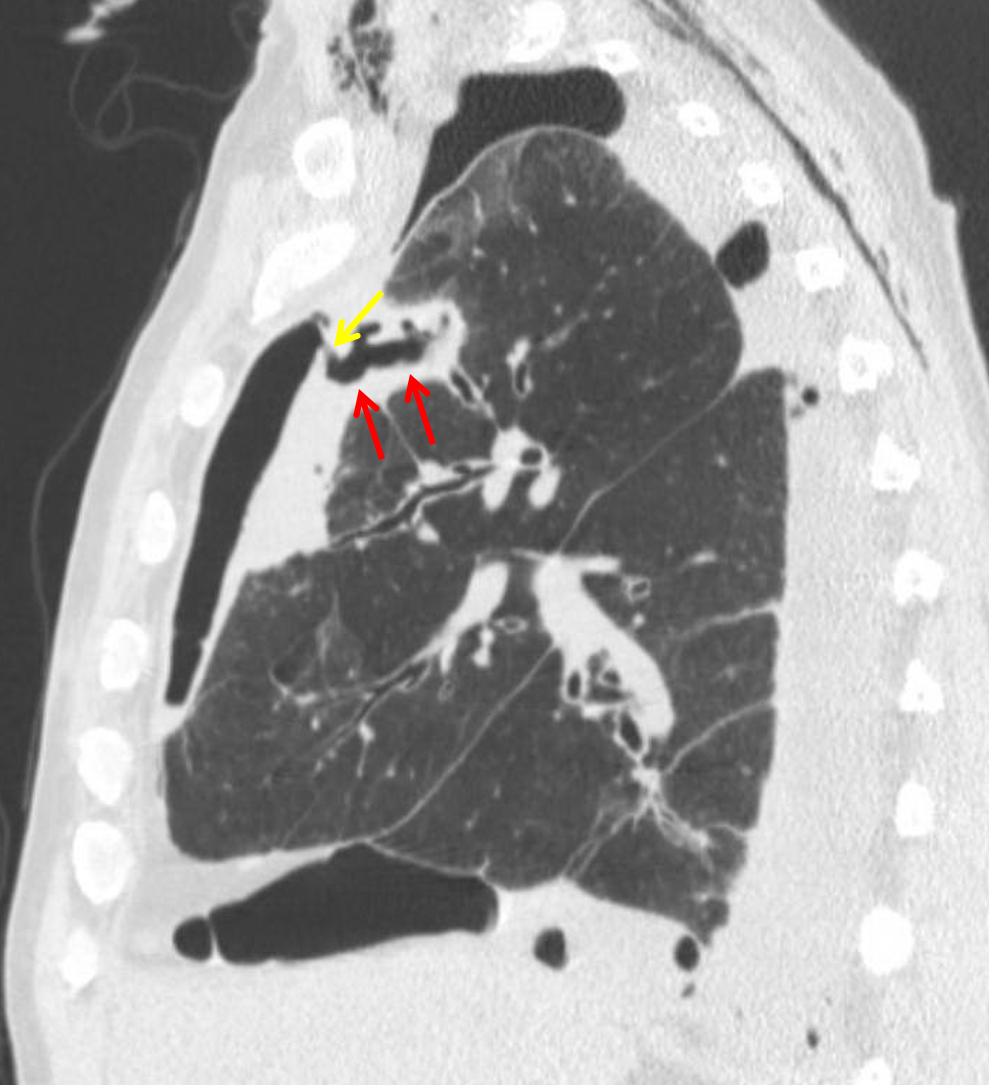

Age: 47

Sex: Male

Indication: Empyema

Sample ReportModerate-sized multiloculated right hydropneumothorax with apically-directed right thoracostomy tube in place, consistent with the clinical suspicion for empyema.

Focal area of consolidation and cavitation in the anterior aspect of the right upper lobe with an associated bronchopleural fistula. This area of consolidation could represent an abscess or cavitary neoplasm.

Extensive right chest wall subcutaneous emphysema.